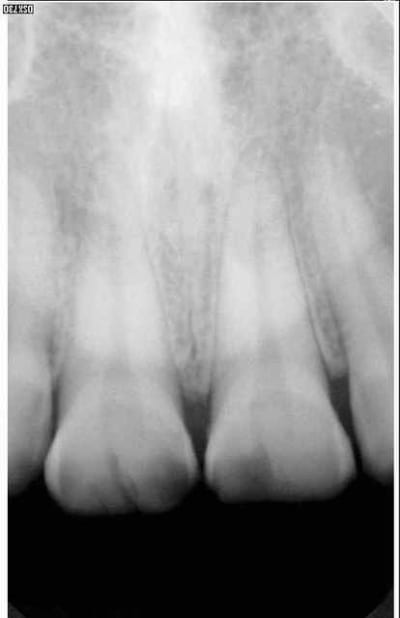

Rvg avant tt xyzyms - Eugenol

A propos d'occluso: Les mylolyses sur 13 et 14 auraient-elles été provoquées par des malocclusions à leur niveau?

On sait que c'est un facteur agravant en tout cas lors des restauration de collet, les dents se "torderaient" lors des explorations létarales, de là à soupconner une fragilité au niveau du collet lors de ces torsions...

C'est cité dans la litterature: les prismes d'email fonctionneraient comme des quartz, avec creation de micro courants qui dans la salive entraineraient leur dissolution. C'est la seule explication raisonnable que j'ai pu lire pour leur etat de surface.